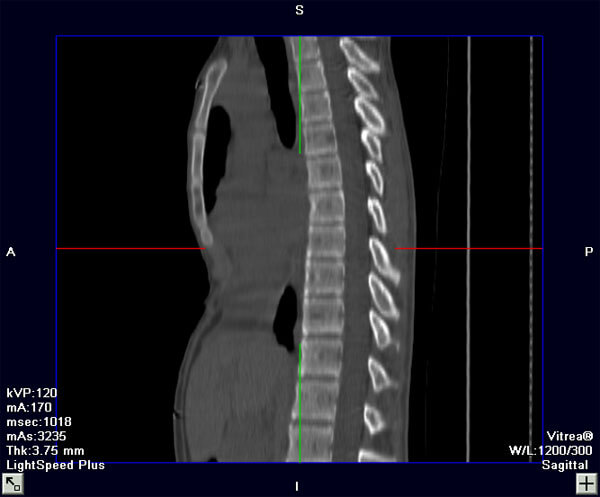

The following are photos and CT images from before and after repair of pectus excavatum.

CT Image (Sagittal View), Before Repair

CT Image (Sagittal View), After Repair